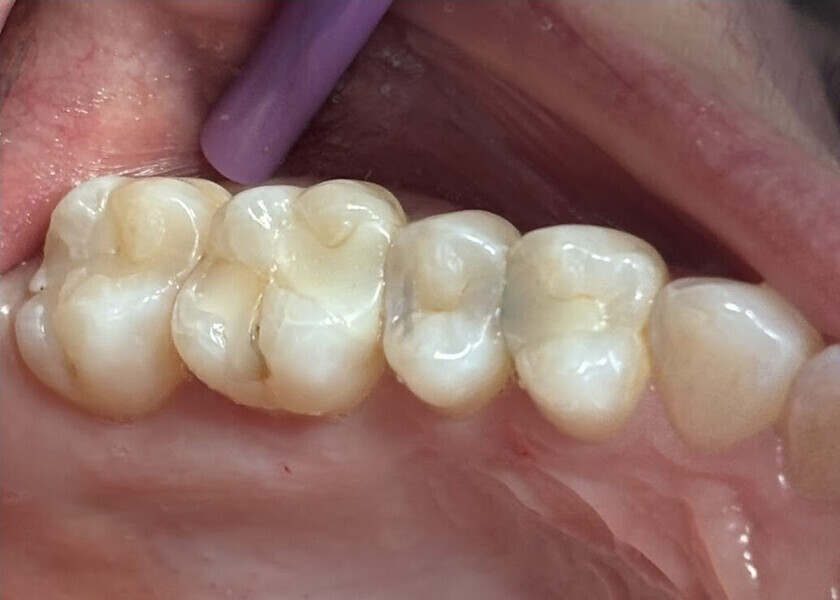

The restorations were taken back to the operatory and tried in to verify fit and seating on the teeth. Once this had been verified, the cementation protocol followed the same procedure detailed in the first case. The completed 3D-printed onlays restored the teeth to natural contours and aesthetics (Fig. 26). A radiograph was taken to confirm marginal adaptation of the luted restorations and elimination of any residual resin cement at the margins (Fig. 27).

Fig. 26: Restorations luted to the prepared teeth after finishing and polishing.